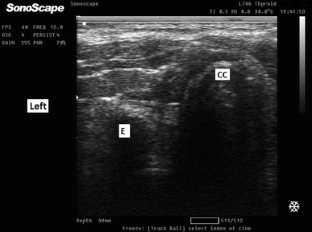

Fig. 2